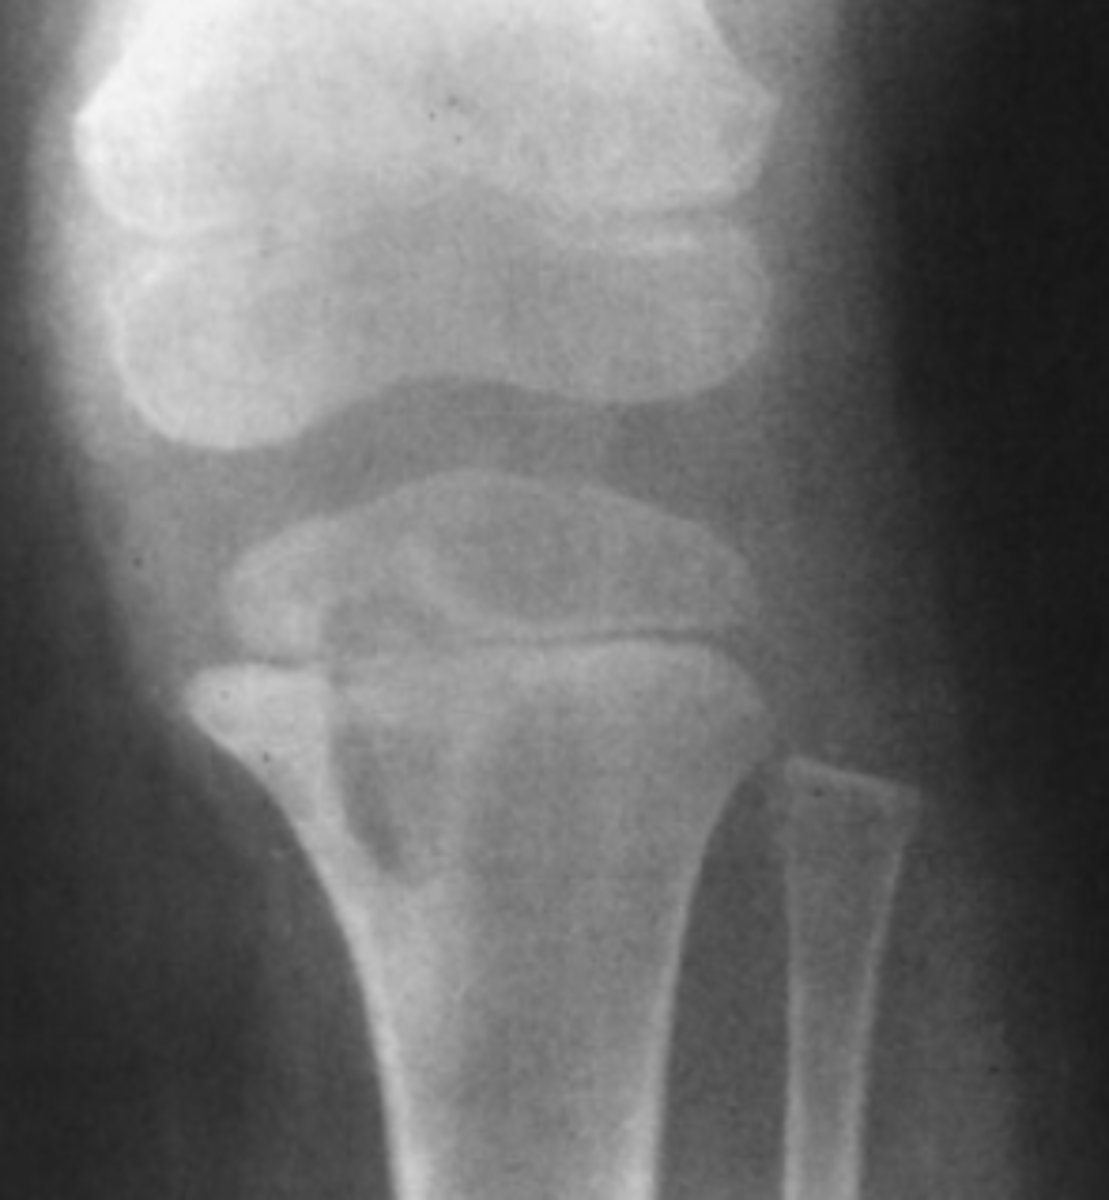

A 40-year-old man complains of knee pain and swelling of 3 weeks' duration. He has no other known disease. You order conventional radiographs of the knee.

For Case 6-11 (Figure 6-29), what is the next study

you should order?

Answer

D.

A thin rim of calcium added to the bony contour of both sides of the right femoral metaphysis due to periosteal elevation. Similar findings are seen on the left femur and both tibiae

Periosteal elevation as seen in 6-11

Nonspecific finding that occurs with local disorders such as fracture, bone tumors, osteomyelitis, and bone infarction.